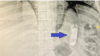

یک تیم از داکتران در شفاخانهٔ تشخیصیهٔ داخلهٔ دانشگاه منصورهٔ مصر یک تلیفون موبایل را از بطن یک زندانی بیرون کردند. این زندانی شش سال پیش تلیفون را بلعیده بود.